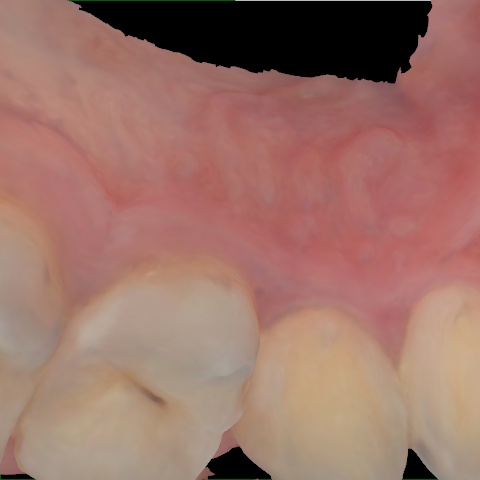

Annotated as "Good"